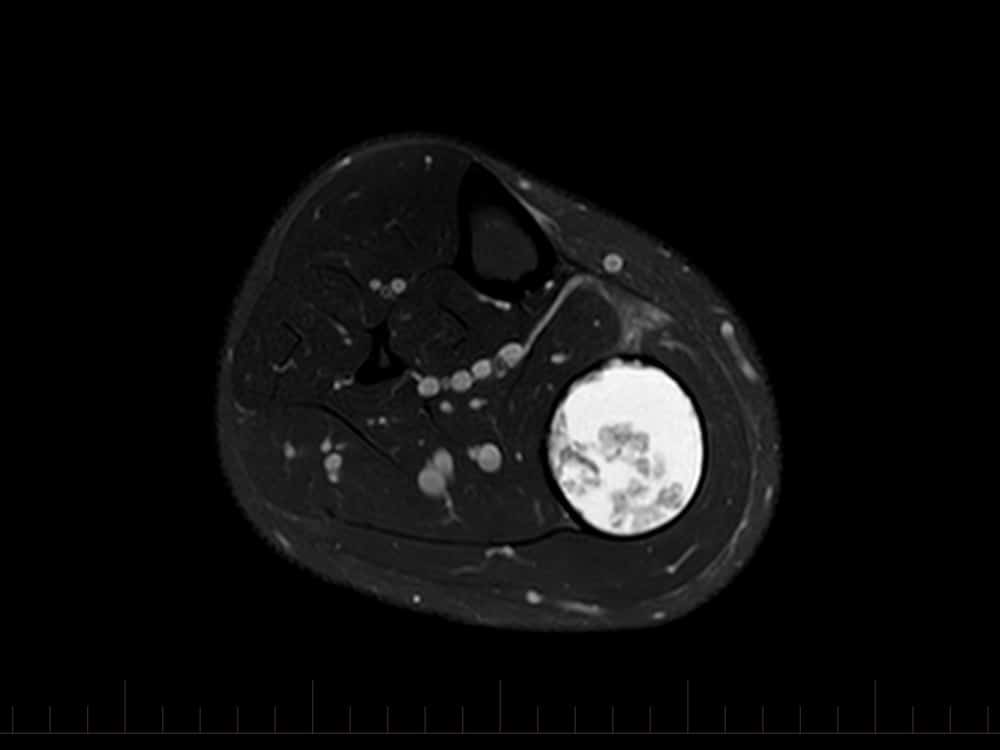

Tụ máu cẳng chân

Tụ máu cẳng chân - Ảnh 2

» Thông tin: Nam giới – 41 tuổi.

» Lâm sàng: Sưng đau cẳng chân / Chấn thương cẳng chân 15 năm.